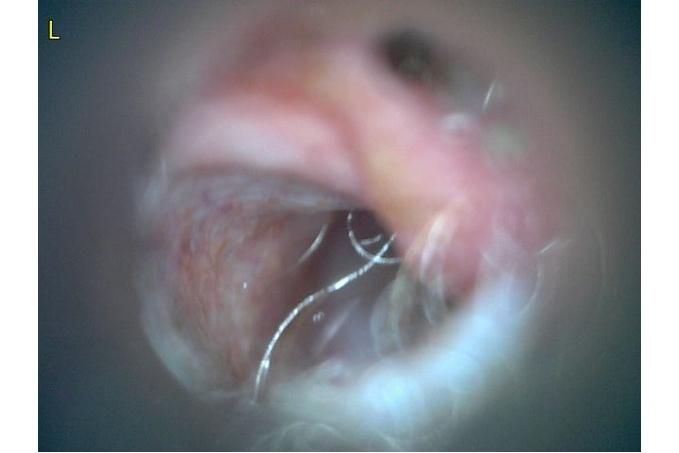

사진만 보고 확진할 수는 없지만 지금 올려주신 귀는 적어도 오른쪽은 정상으로 보이기 어렵습니다 왼쪽은 비교적 연분홍에 가까워 보이지만 오른쪽은 털과 분비물이 많이 차 있고 피부가 자극받은 듯한 모습이라 외이염 가능성을 먼저 생각하게 됩니다 그리고 질문자님이 적어주신 머리 털기 하루 여러 번 귀 만질 때 통증 솜만 닿아도 예민함 귀 긁기 같은 증상은 외이염에서 흔한 신호입니다

다만 이 사진만으로 중이염이나 내이염이라고 단정할 수는 없습니다 중이염이나 내이염은 귀 통증과 머리 털기만으로도 올 수 있지만 보통은 고개 기울어짐 비틀거림 안구가 흔들리는 증상 얼굴 한쪽 처짐 같은 더 깊은 신경 증상이 같이 보일 때 더 의심합니다 지금 적어주신 내용만 보면 제일 먼저는 오른쪽 외이도 염증과 통증 조절이 우선으로 보입니다

지금 제일 조심해야 할 것은 귀세정을 무조건 하는 것도 무조건 안 하는 것도 아니라는 점입니다 고막 상태를 확실히 모르는 귀에 자극적인 세정제를 넣거나 세게 세정하면 더 아프고 더 깊은 쪽을 자극할 수 있습니다 특히 알코올 성분 세정제는 염증 있는 귀에서 따갑고 자극적일 수 있고 고막이 손상돼 있으면 더 문제가 될 수 있습니다 그래서 지금처럼 오른쪽이 아픈 귀는 집에서 강하게 세정하는 쪽은 저는 말리고 싶습니다